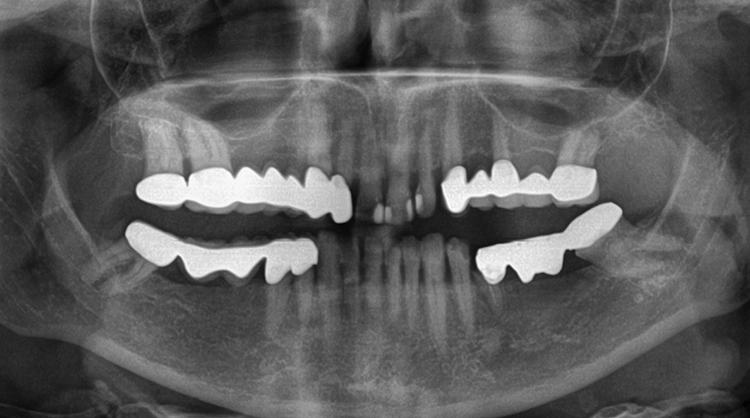

Eine 63-jährige Patientin stellte sich mit einer schon seit längerer Zeit bestehenden Schaltlücke im Unterkiefer links vor. Ziel der geplanten Behandlung war die adäquate prothetische Neuversorgung mittels einer implantatgetragenen Brücke (Abb. 1).